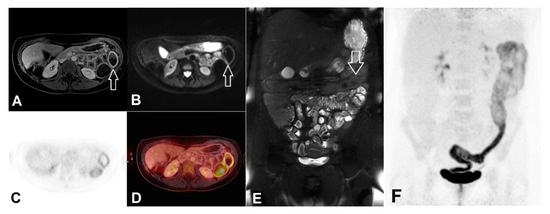

3.6. Extra-Intestinal Findings